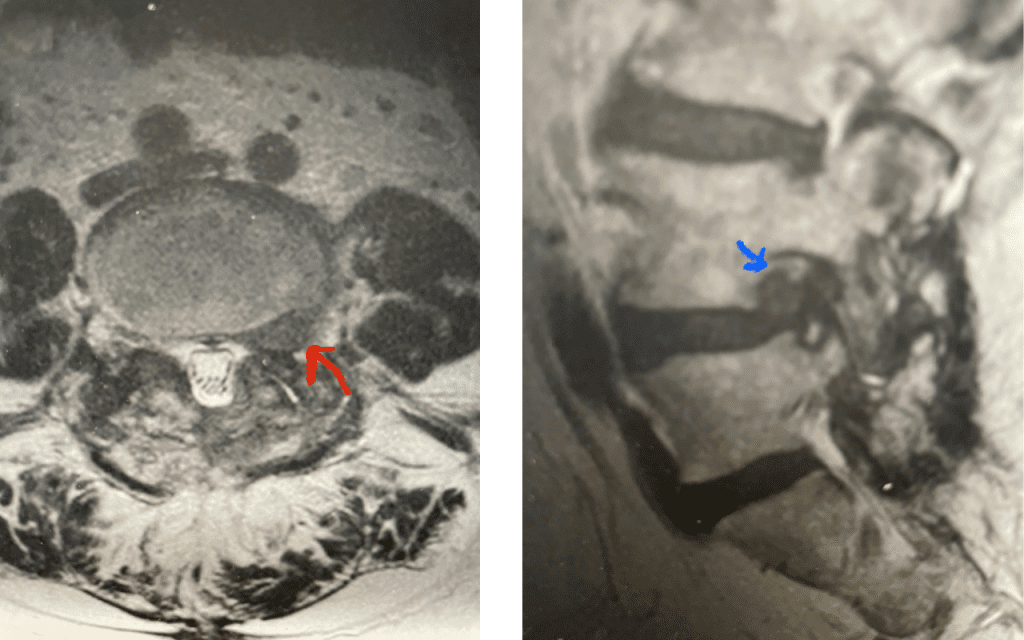

Here is a case of an extraforaminal disc fragment causing severe pain and weakness: This 60-year-old male presented with severe anterior thigh pain, numbness, and weakness for 3 weeks. He had failed epidural steroid injections. His left leg buckled when he walked. Imaging revealed a massive left L3-4 extraforaminal disc herniation, beyond the facet (Fig 6). This was severely compressing the left L3 nerve root in the L3-4 foramen (Fig 7). It was felt that the patient required surgery, as he would not be able to participate in physical therapy and had a neurological deficit. We performed an extraforaminal approach and removed a massive disc fragment that was revealed as the intertransverse membrane was reflected from the L4 transverse process-facet junction. We were able to visualize the L3 spinal root exiting above that had been compressed by the large fragment we removed (Fig 8). The patient post-op had a dramatic improvement neurologically and with significantly improved pain in his leg.

Fig 6: Axial T2-weighted lumbar MRI revealing a large extraforaminal disc herniation with severe compression of the left L3 nerve (red arrow).

Fig 7: Sagittal T2-weighted lumbar MRI with side by side comparison of the normal open right L3-4 foramen (red arrow) compared to the left L3-4 foramen filled with a large disc fragment (red arrow).